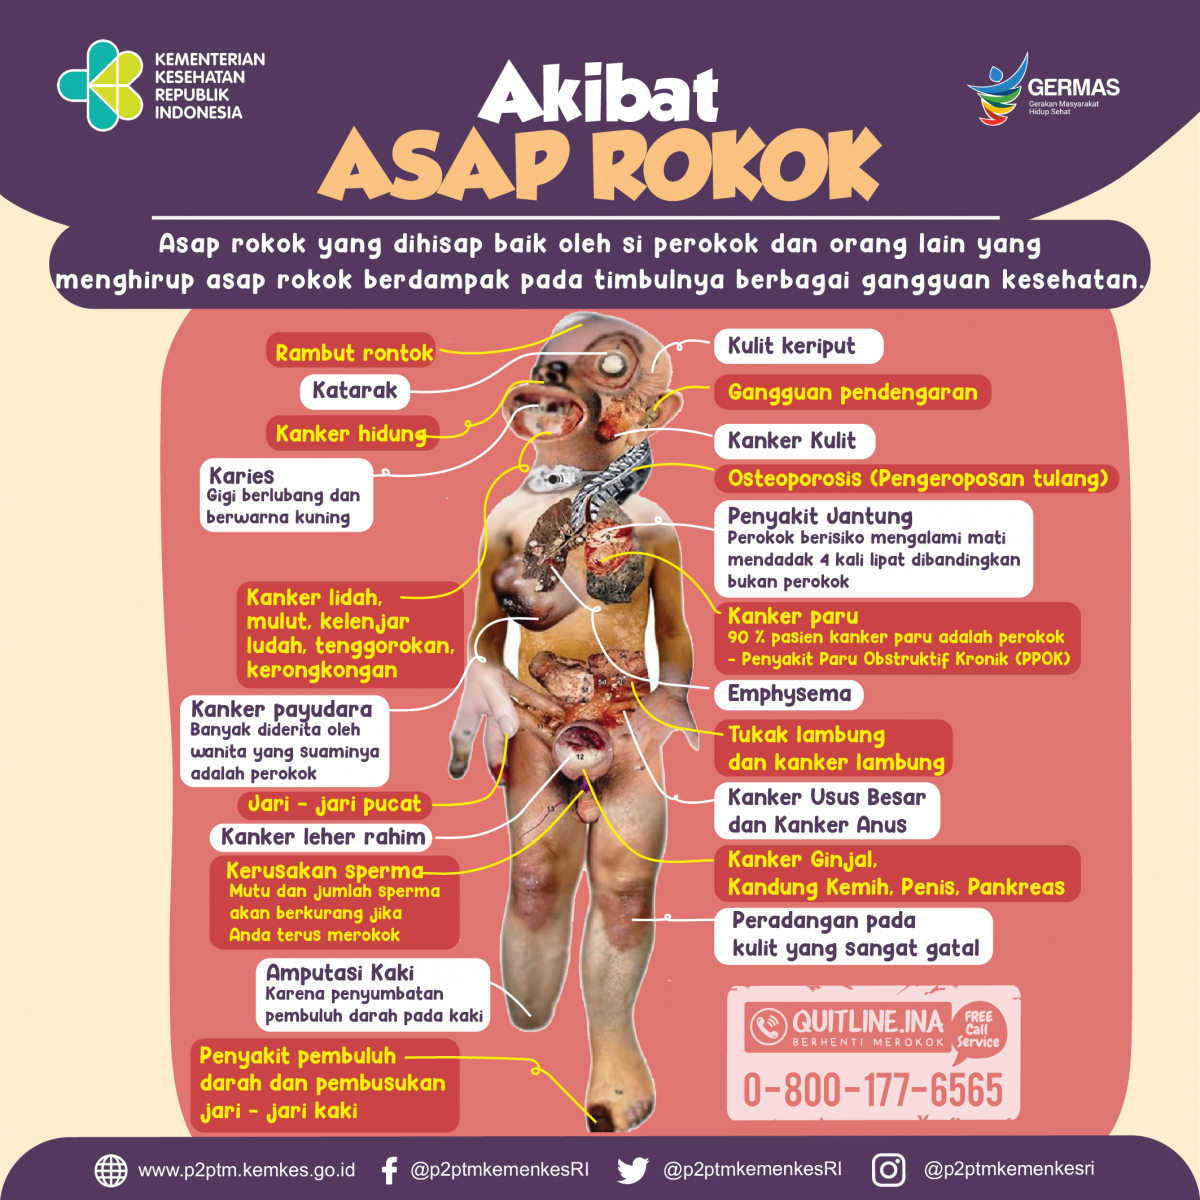

Akibat Asap Rokok Direktorat P2ptm

Akibat Asap Rokok Direktorat P2ptm

Gambaran Akibat Asap Rokok Direktorat P2ptm

Gambaran Akibat Asap Rokok Direktorat P2ptm

Akibat Asap Rokok Direktorat P2ptm

Akibat Asap Rokok Direktorat P2ptm

Apa Saja Akibat Asap Rokok Direktorat P2ptm

Apa Saja Akibat Asap Rokok Direktorat P2ptm